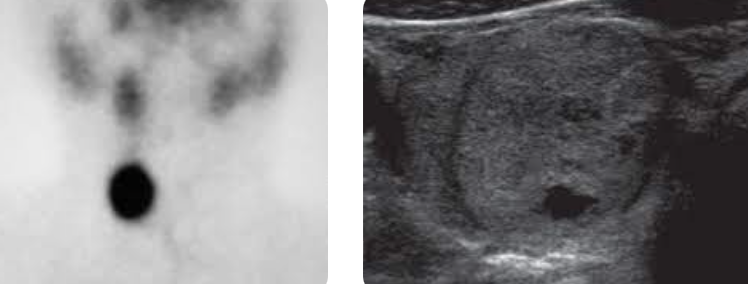

Thyroid ultrasound

A

Think hyperfunctioning (toxic) adenoma

Note: Mostly solid thyroid nodule that is hot on I-123 scan (nodule uptake with relatively suppressed background thyroid uptake).